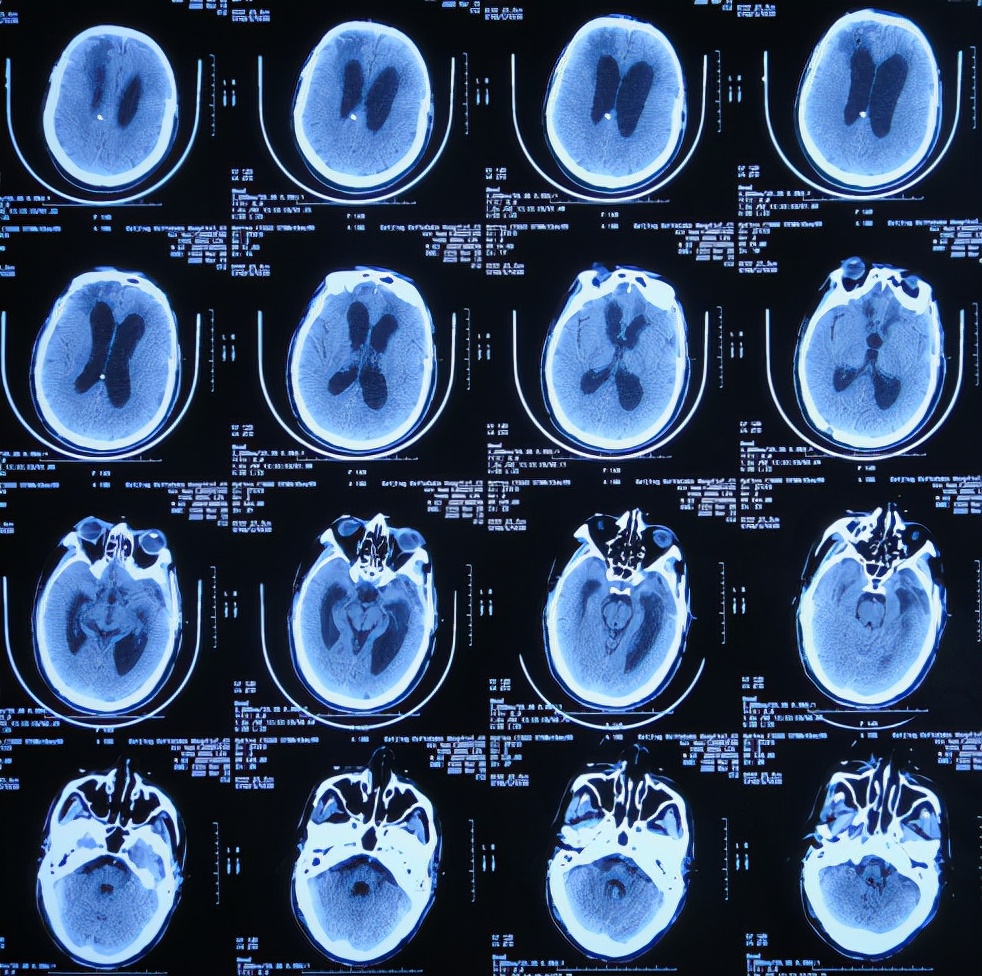

2019年10月20日患者骑电动车在马路上行驶时被大货车撞倒,当时意识清楚,只感到有些头晕,未在意就自行回家,但回家后约3-4小时出现头晕加重,并伴有恶心呕吐的症状,家人急送到当地的河北省邯郸市某医院,查头颅CT示脑出血( 图-1 );既往病史2015年曾因头部外伤致硬膜下血肿,进行了钻孔引流术。

图-1: 2019年10月20日头颅CT

急诊进行了开颅去骨瓣血肿清除术,术后次日查头颅CT示去骨瓣术后( 图-2 )。

图-2: 2019年10月21日头颅CT

开颅术后第2天即2019年10月22日,仍昏迷,查头颅CT示积血未见减少( 图-3 ),给予腰椎穿刺术。

图-3: 2019年10月22日头颅CT

开颅术后第4天即2019年10月24日,查头颅CT示积血仍未明显减少( 图-4 )。

图-4: 2019年10月24日头颅CT